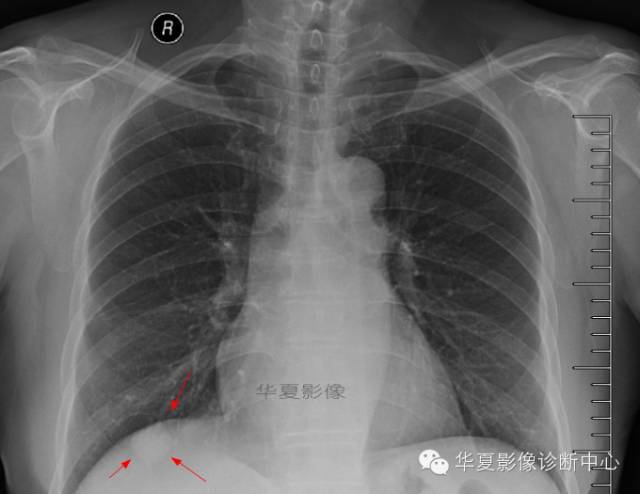

简要病史:女,66岁,因“咳嗽10天”入院。

病例特点:患者10天前受凉后出现咳嗽,干咳为主,偶咳少量黄色粘痰,咳嗽剧烈时感胸痛,无发热、咯血、盗汗、胸闷、气喘、心前区不适、恶心、呕吐、腹痛、腹泻、尿频、尿急等不适,在家自服感冒药,咳嗽缓解不明显,肿瘤全套:癌胚抗原高1.92ng /ml 神经元烯醇化酶 10.11ng /ml 细胞角蛋白19片断2.64ng /ml 给予抗感染(可乐必妥)等对症处理后,以“右肺占位”收入我科。患者目前精神尚可,体力正常,食欲正常,睡眠正常,体重无明显变化,大便正常,排尿正常。

影像资料: